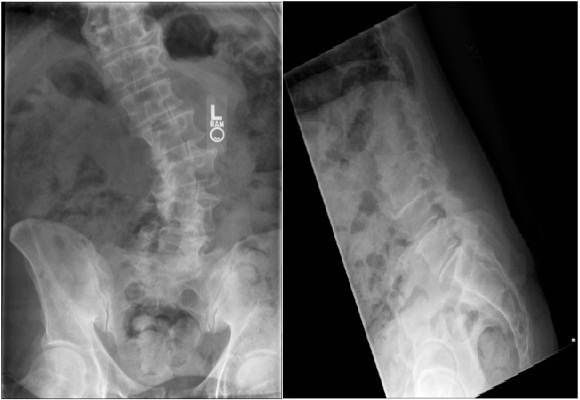

Adolescent Idiopathic Scoliosis (Type 3)

20 yr Gymnast